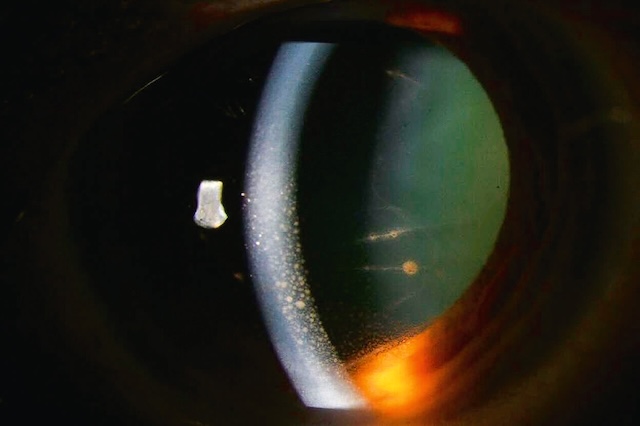

La symptomatologie est brutale et bruyante, avec des douleurs oculaires et une baisse d’acuité visuelle souvent profonde. Les douleurs oculaires peuvent s’accompagner de nausées et de vomissements. À l’examen macroscopique, l’œil est rouge, et la pupille souvent en semi-mydriase non réactive à la lumière. L’examen ophtalmologique met en évidence une acuité visuelle diminuée, une pression intraoculaire (PIO) élevée (plus de 30 mmHg), appréciable par la palpation bidigitale du globe oculaire à travers la paupière supérieure (sensation de bille de bois). On observe une hyperhémie conjonctivale avec un cercle périkératique, un œdème de cornée, une chambre antérieure peu profonde et en gonioscopie un angle irido-cornéen fermé (e-fig.8.1).

Une fois la PIO normalisée et l’œdème de cornée réduit, une iridotomie laser est réalisée de façon à éviter une récidive (fig. 8.2). Une iridotomie préventive de l’œil controlatéral est également réalisée de façon systématique.

Photographie prise en lampe à fente montrant une rubéose irienne majeure, dans un contexte d’occlusion veineuse centrale de la rétine (OVCR) ischémique. On observe, sur toute la surface de l’iris, une prolifération néovasculaire marquée, avec de multiples vaisseaux rouges fins, anormaux, irradiant depuis le bord pupillaire vers la périphérie irienne. Ces néovaisseaux s’étendent en arborisation dense, soulignant un état d’ischémie rétinienne sévère responsable d’un appel vasoprolifératif antérieur. La chambre antérieure est légèrement floutée, traduisant une réaction inflammatoire ou un début de glaucome néovasculaire. Le reflet pupillaire est diminué, avec un cristallin partiellement opacifié, et l’hyperhémie conjonctivale périphérique accentue le caractère pathologique global. L’image exprime de façon frappante la gravité de la situation, la rubéose étant souvent annonciatrice de complications majeures telles qu’un glaucome néovasculaire menaçant la fonction visuelle.